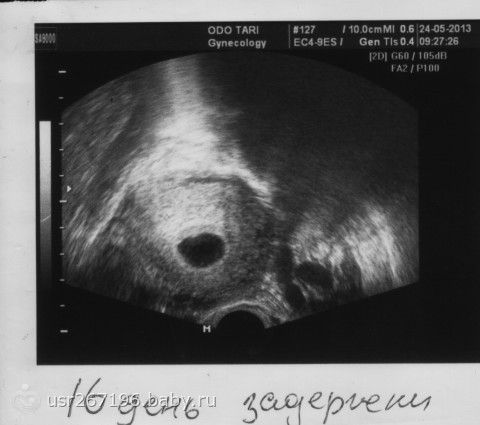

Всем привет, была я сегодня на узи, главное что б маточная, и бьётся сердечко, вот моя радость

фото переворачивается почему то, но ничего… главное мне повернули монитор и показали как бьётся сердечко(особенно девочкам, которых интересовал вопрос на каком сроке его слышно)

То что киста, врач пояснила к недели 16 рассосётся, просто видно две яйцеклетки выходило, ну и после моего воспаления несколько месяцев назад видно тоже что-то дало.Я теперь знаю почему в о сильно живот резало, и сейчас иногда побаливает слева… ну да ладно, врач очень приятная женщина, я ей вопрос, она ответ, умничка, пояснила, а то я переживала что да как, да киста откуда

Главное беременность маточная, сердце бьётся, дата ПДР прикольная, а я счастлива, чего и всем беременным желаю